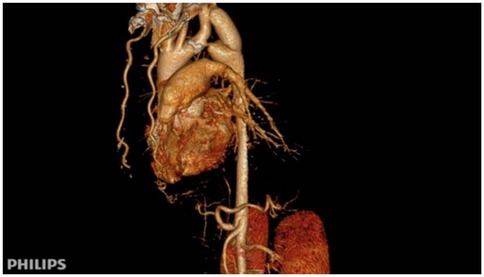

After comprehensive evaluation and multidisciplinary team (MDT) discussion, surgical correction was deemed necessary. Given the patient's age, vascular anatomy, and the extent of aortic interruption with heavy calcification, endovascular intervention was considered unfeasible. An extra-anatomic bypass procedure using a left subclavian artery-to-descending aorta synthetic graft was selected as the optimal approach. The left subclavian artery, with an internal diameter of 15 mm, was suitable as the proximal anastomosis site. A post-stenotic aneurysm of the descending aorta was also noted, measuring approximately 54.0 mm × 33.2 mm in maximal cross-sectional diameter.

Figure 5

Scattered calcified plaques are observed in the walls of the aortic arch and brachiocephalic trunk, with irregular lumens as shown in (A). The descending aorta shows poststenotic aneurysmal dilation, with dimensional measurements provided in (B).